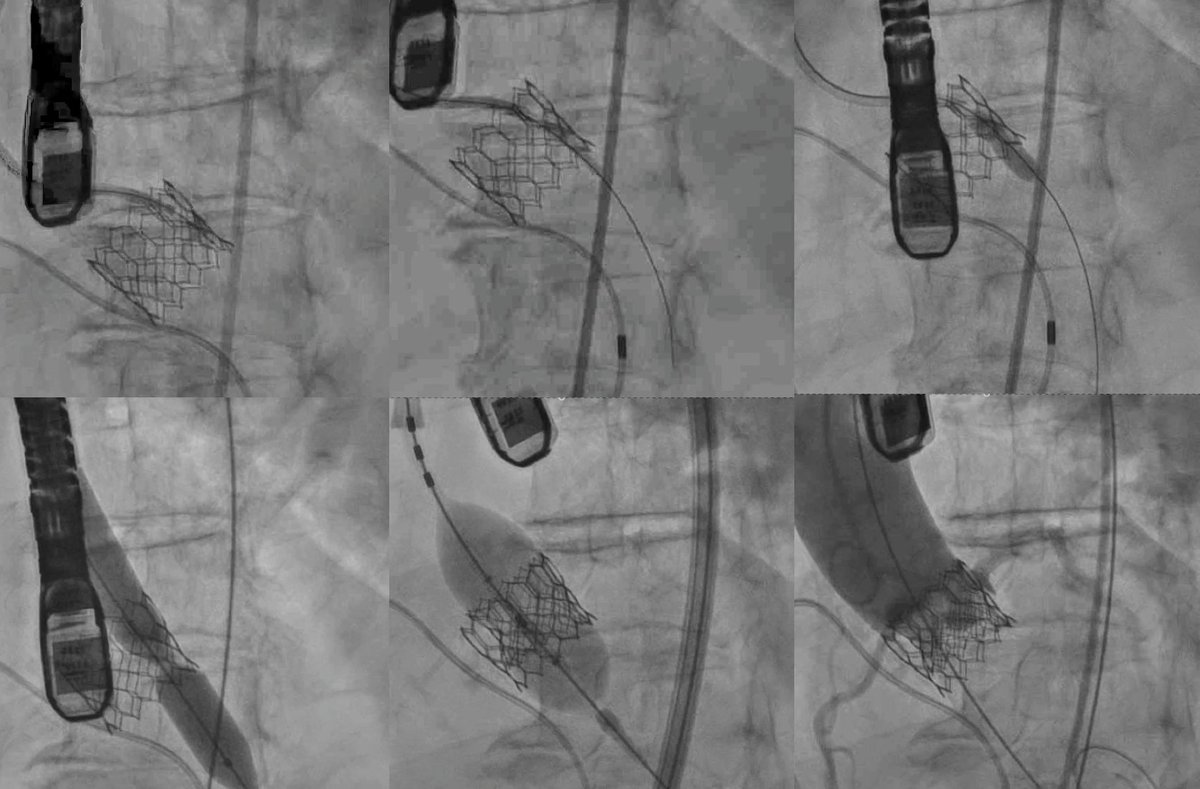

Congrats #JenaValve on their @US_FDA approval of JenaValve #TAVR for pure AR in high risk pts. A huge milestone for pts with pure AR not candidates for surgery.